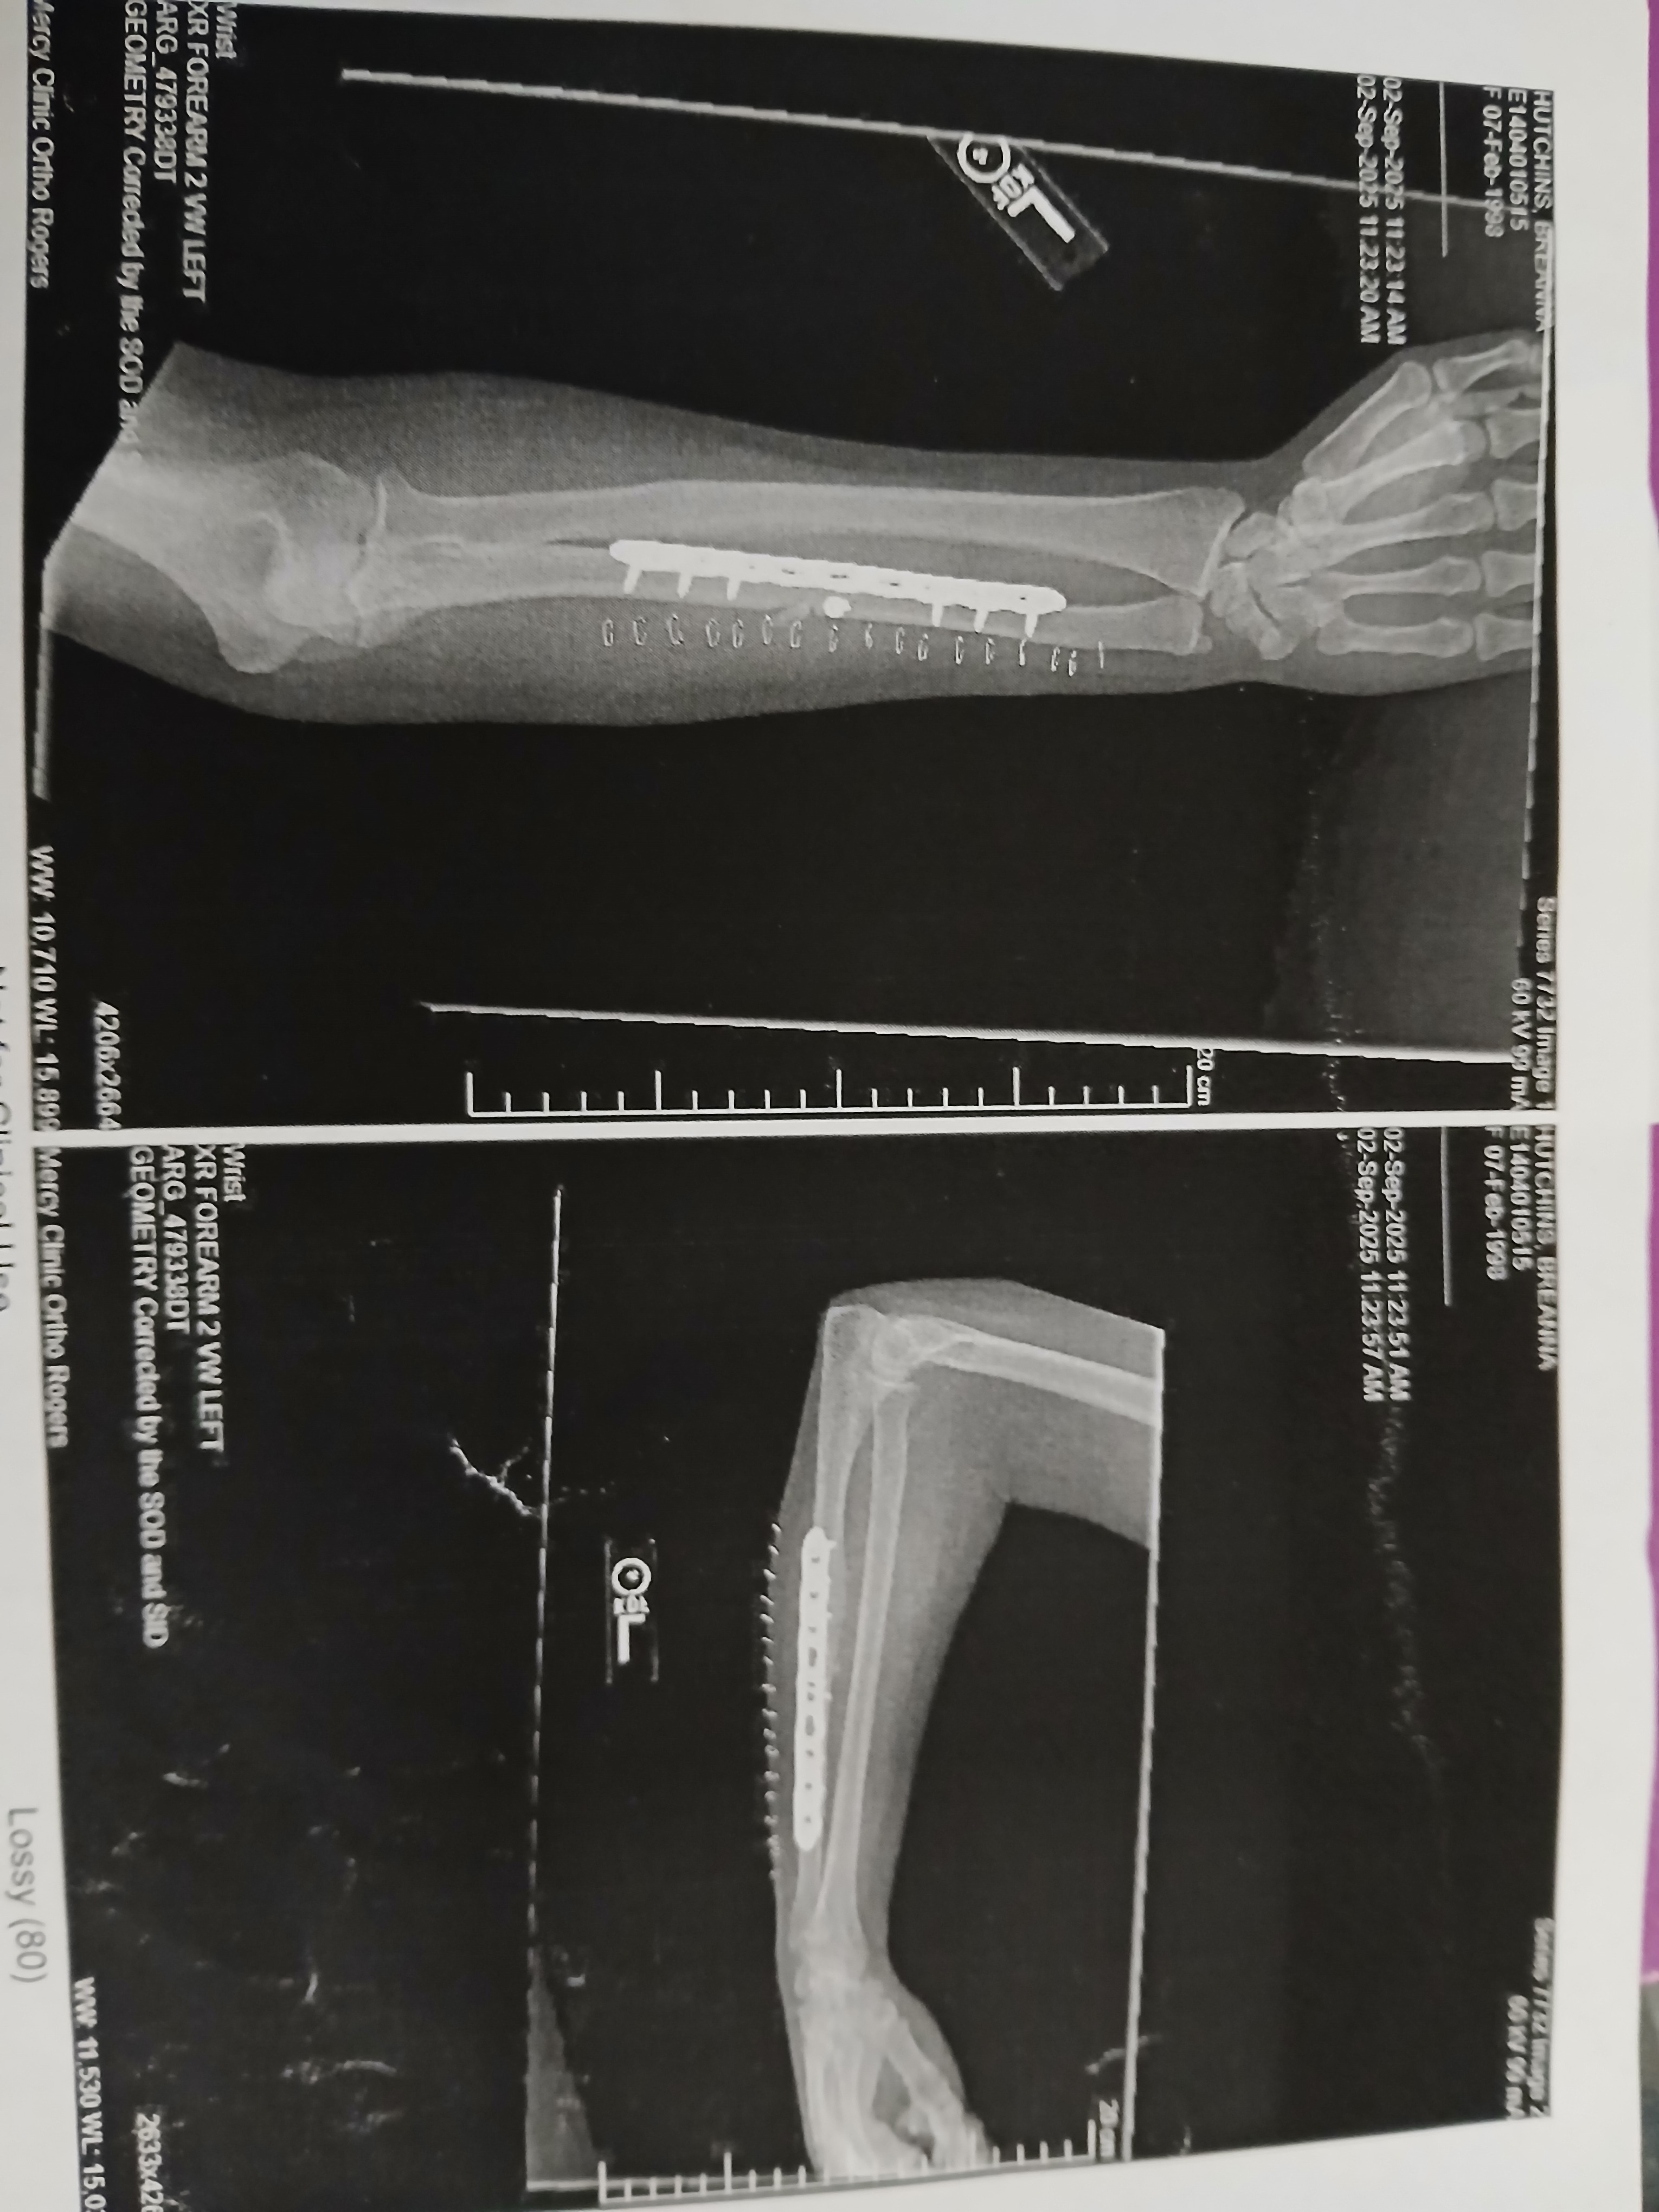

Hi, my name is Breanna, and I never thought I’d be making one of these. On August 14th, my life changed forever when I was in a major car accident where I was the sole survivor and it nearly took everything from me. I spent time in the ICU with multiple life-threatening injuries, including a broken back in five places, a broken neck, eight broken ribs, a broken arm (with a plate put in), internal bleeding, a lacerated liver and pancreas, and a ruptured spleen that had to be removed. I also had a trach put in to help me breathe while doctors drained over 64 ounces of fluid from my lungs.